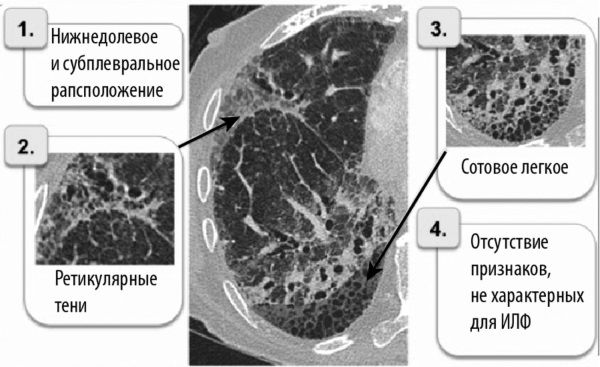

В диагностике используют:

- рентгенологическое исследование легких (лучше компьютерную томографию, если есть возможность);

По результатом обследований наблюдаются фиброзные очаги (тяжи, рубцы) и значительное снижение функции легких.

На рисунке показано, как выглядят фиброзные изменения в легких.